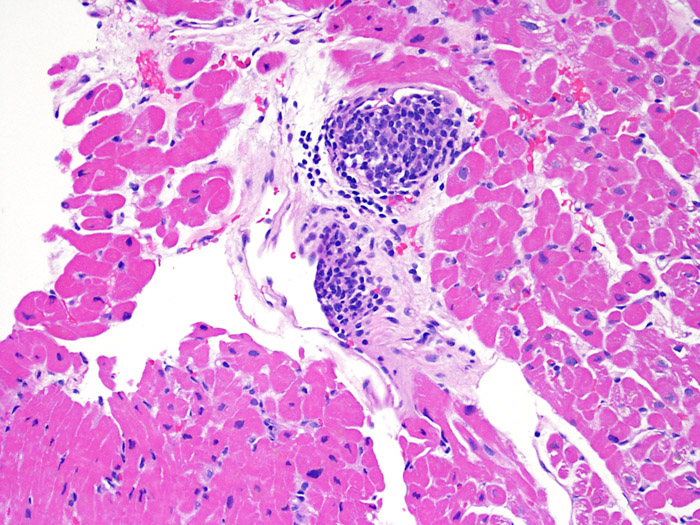

Межуточный миокардит: гистологические исследования